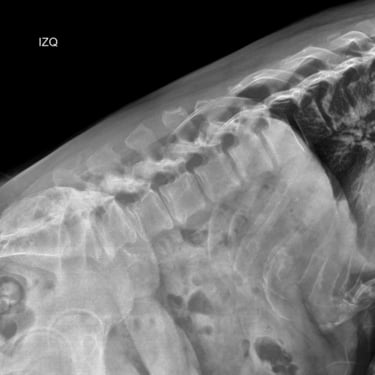

Columna lumbar inestable con listesis: tratamiento con artrodesis y tornillos transpediculares

La listesis lumbar ocurre cuando una vértebra se desplaza hacia adelante o hacia atrás respecto a la vértebra inferior, generando inestabilidad de la columna lumbar. Esta condición puede causar dolor lumbar crónico, compresión nerviosa, ciática, debilidad en las piernas o dificultad para caminar. Cuando el tratamiento conservador no es suficiente, la artrodesis lumbar con tornillos transpediculares es una alternativa quirúrgica eficaz. Este procedimiento permite fijar las vértebras afectadas mediante implantes que estabilizan la columna y favorecen la fusión ósea. Con técnicas modernas y abordajes mínimamente invasivos, se logra aliviar el dolor, mejorar la estabilidad vertebral y recuperar la función del paciente.